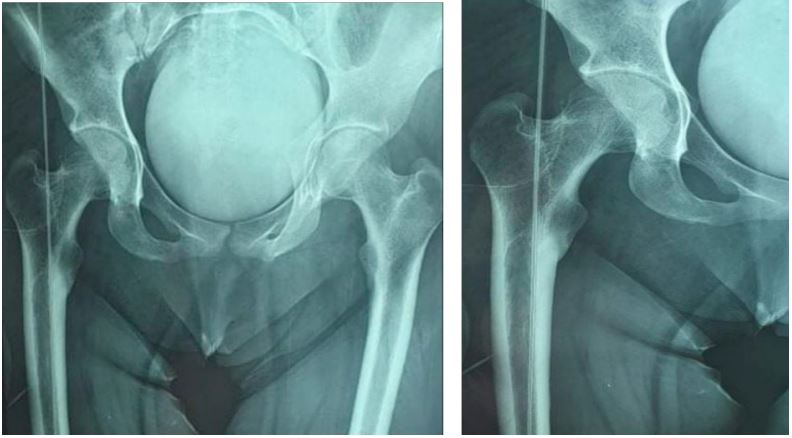

Radiological assessment confirmed a pure posterior right iliac hip dislocation (Figure 1).

Figure 1: Pure posterior right iliac hip dislocation.